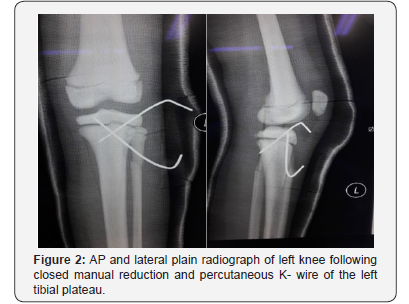

Ms A, an eight- year old girl met in a road traffic accident (motorcycle versus car). She was the pillion rider on a motorcycle rode by her sister. While making a U-turn, the front of their motorcycle was hit by a car at the speed of 30-40kmPH causing them to lose control of the motorcycle and she fell sideways landing on her left knee. There was no direct impact to her. She presented to the emergency department with complain of left knee pain, swelling and inability to weight bare. She was diagnosed with closed left tibial plateau fracture salter Harris type two and proximal third fibula fracture (Figure 1). She underwent closed reduction and percutaneous K-wiring of her left proximal tibia (Figure 2) which subsequently was complicated with osteomyelitis (Figure 3). On retrospective review of her initial plain radiograph, it was noticed to show generalized increase in bone density.